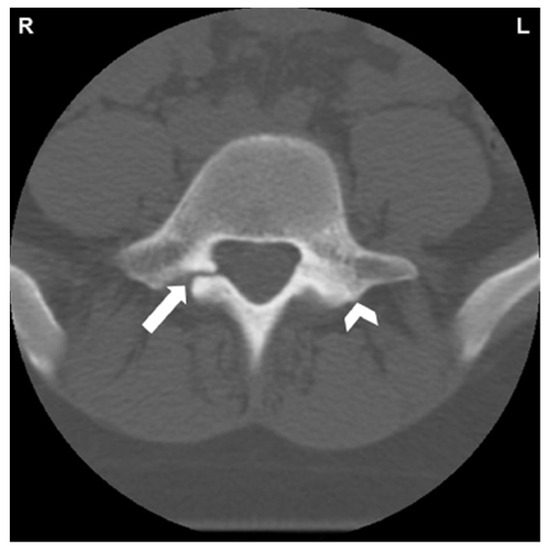

- Fayed, I.; Conte, A.G.; Voyadzis, J.-M. Success and failure of percutaneous minimally invasive direct pars repair: Analysis of fracture morphology. World Neurosurg. 2019, 126, 181–188. [Google Scholar] [CrossRef]

- Ghobrial, G.M.; Crandall, K.M.; Lau, A.; Williams, S.K.; Levi, A.D. Minimally invasive direct pars repair with cannulated screws and recombinant human bone morphogenetic protein: Case series and review of the literature. Neurosurg. Focus 2017, 43, E6. [Google Scholar] [CrossRef] [PubMed]